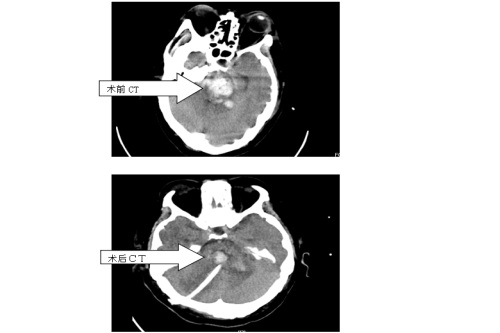

患者入院时呈神志深昏迷状态,GCS4分,CT提示脑干出血。脑干出血是脑出血中最凶险的一种,一直被认为是手术禁区,患者死亡率及致残率极高,以前传统治疗均为给予药物保守治疗。近年来有些大医院开展开颅手术清除血肿,但并不能改善患者预后,没有得到广泛推广。经过与患者家属充分沟通,神经外科赵浪平主任医师带领张国斌副主任医师,周嘉敏、黄启伟主治医师,朱鹏博医师等一起为患者行“脑干出血立体定向下穿刺外引流术”。该手术具有恢复快、住院时间短、治疗费用低等优点,是一种创伤小、治疗确切、家属容易接受的治疗手段。

临床医学院/附属医院自引进新的立体定向仪以来,就已开展了多例“脑出血”的“立体定向脑内血肿置管外引流术”,均取得了成功。立体定向仪不但可以行脑出血“靶向”治疗,对于颅内微小病变及无法明确诊断的病变也可进行“靶向”下活检,还可以立体定向下脑内放疗置入、脑内深部电刺激、脑内深部电极置入、帕金森病的毁损和电极置入等治疗,它具有创伤小、定位准确、费用低的优点。此次该院神经外科进行的“脑干出血立体定向下穿刺外引流术”为九江地区自主进行的第一例该种手术,标志该院神经外科又向前迈出了坚实的一步。